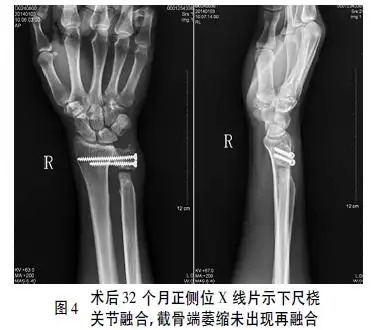

sauvékapandji术治疗陈旧性下尺桡关节掌侧脱位1例报告并文献复习